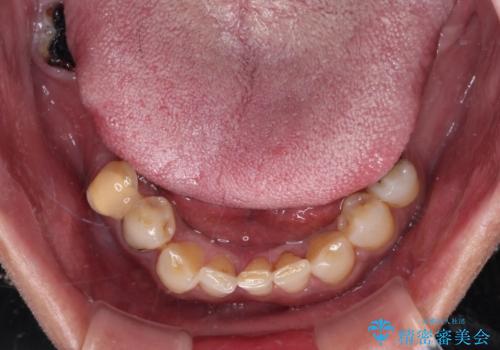

- 奥歯の欠損や、ボロボロになった歯を気にして来院された患者様です。

転勤で東京にいる1年間の間に治療を終えたいとのことで、奥歯のインプラント埋入や前歯部の歯周外科処置など、治癒に時間を要するものから始めていき、治癒期間に根管治療や補綴治療を進めて行くこととしました。

インプラントにより奥歯の咬み合わせが安定し、上顎前歯の歯肉ラインを調整するための骨外科処置により深く咬みこんでいた前歯部も負担のかからない咬み合わせに改善することができました。